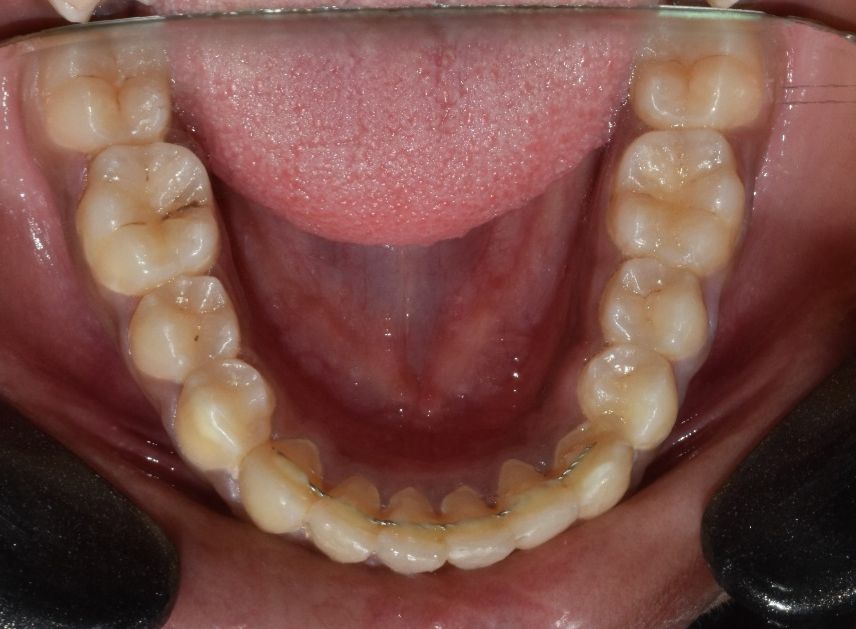

Before & After Results

At Aline Dent, we take pride in delivering visible and lasting improvements in our patients’ smiles. Our before-and-after results highlight the effectiveness of modern dental treatments combined with personalized care. This gallery showcases real dental cases treated at our clinic, giving you a clear idea of how different dental concerns can be corrected with the right treatment approach.

From minor corrections to complete smile enhancements, these teeth transformation results demonstrate how professional dental care can improve both oral health and appearance. Our experienced dental team carefully evaluates each patient’s needs and creates customized treatment plans to achieve natural, healthy, and confident smiles.

In this gallery, you will find a variety of smile makeover cases, including treatments for crooked teeth, gaps, discoloration, damaged teeth, and other common dental concerns.